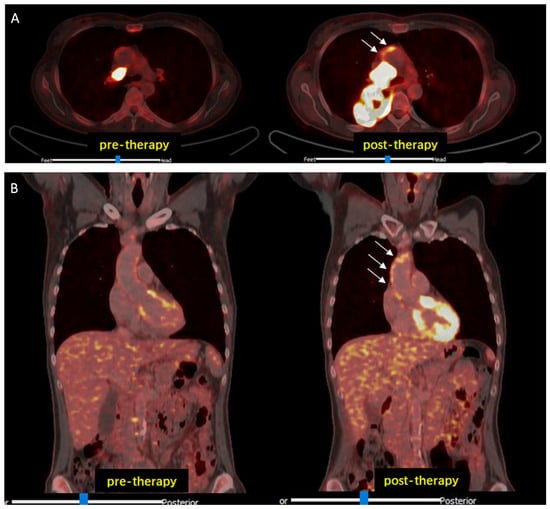

Figure 1. Representative 2-[18F]FDG PET/CT images. Increased arterial 2-[18F]FDG uptake (white arrows) after ICI therapy compared to baseline examination (pre-therapy) observed in transaxial (A) and in coronal (B) views. Abbreviations: CT, computed tomography; 2-[18F]FDG, 2-[18F]fluorodeoxyglucose; ICI, immune checkpoint inhibitors; PET, positron emission tomography.

Cancer immunotherapy with ICI resulted in a modest but significant increase in 2-[18F]FDG-uptake in all analyzed arterial PET lesions (n = 761; lesional TBRpre = 1.73 ± 0.42 vs. lesional TBRpost = 1.90 ± 0.44; p < 0.001), interpreted as inflammatory activity (Figure 1).